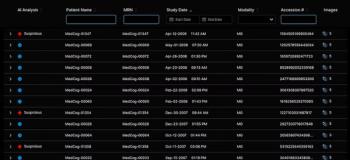

By combining a deep neural network trained on chest X-rays with routine clinical variables, researchers from New York University Langone (NYU Langone) have created a system that performs comparably to interpreting radiologists and that can predict with 80-percent accuracy which COVID-19-positive patients will deteriorate, including mortality, intubation, and ICU admission.

To create the neural network, the team used a training set of 5,224 chest X-rays from 2,943 patients who had severe COVID-19. With those images, they trained two models – one based on the Globally-Aware Multiple Instance Classifier (COVID-GMIC) and another based on a gradient boosting model (COVID-GBM).

Their test set consisted of 770 images from 718 patients who were admitted to NYU Langone between March 3, 2020, and June 28, 2020.

Based on their analysis, the team calculated the area under the receiver operating characteristic curve (AUC) and the area under the precision-recall curve (PR AUC) for deterioration prediction within 24, 48, 72, and 96 hours from the time of the chest X-ray. They, then, compared the system’s performance to outcomes produced by two radiologists.

Their main outcome, the team said, is that the deep neural network system outperforms the radiologists in terms of AUC and PR AUC at 48, 72, and 96 hours. Specifically, the COVID-GMIC achieved an AUC of 0.808 at 96 hours compared to 0.741 of both radiologists. This performance shows that the computer program accurately predicts four out of five cases where an infected patient will either require intensive care or mechanical ventilation or die within four days of admission.

Geras’s team also sought to take their deep neural network one step further, pushing it to overcome the existing clinical implementation hurdle. On May 22, 2020, they silently deployed their system into the hospital where it was able to produce predictions in real-time in approximately two seconds.

Between the launch date and June 24, 2020, they collected 375 chest X-rays – 38 of which (10.1 percent) were associated with a positive 96-hour deterioration outcome. This outcome is lower than the 20.3 percent in the retrospective test set, but the differences are expected, the team said, due to potential patient differences and changing treatment guidelines as the pandemic progressed.